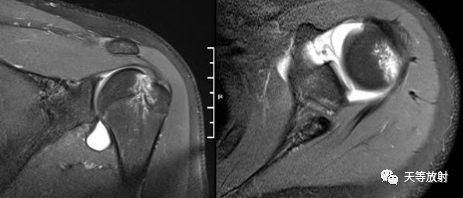

MR间接关节造影1.5T轴位T1W脂肪抑制

MR间接关节造影1.5T冠状面T1W脂肪抑制